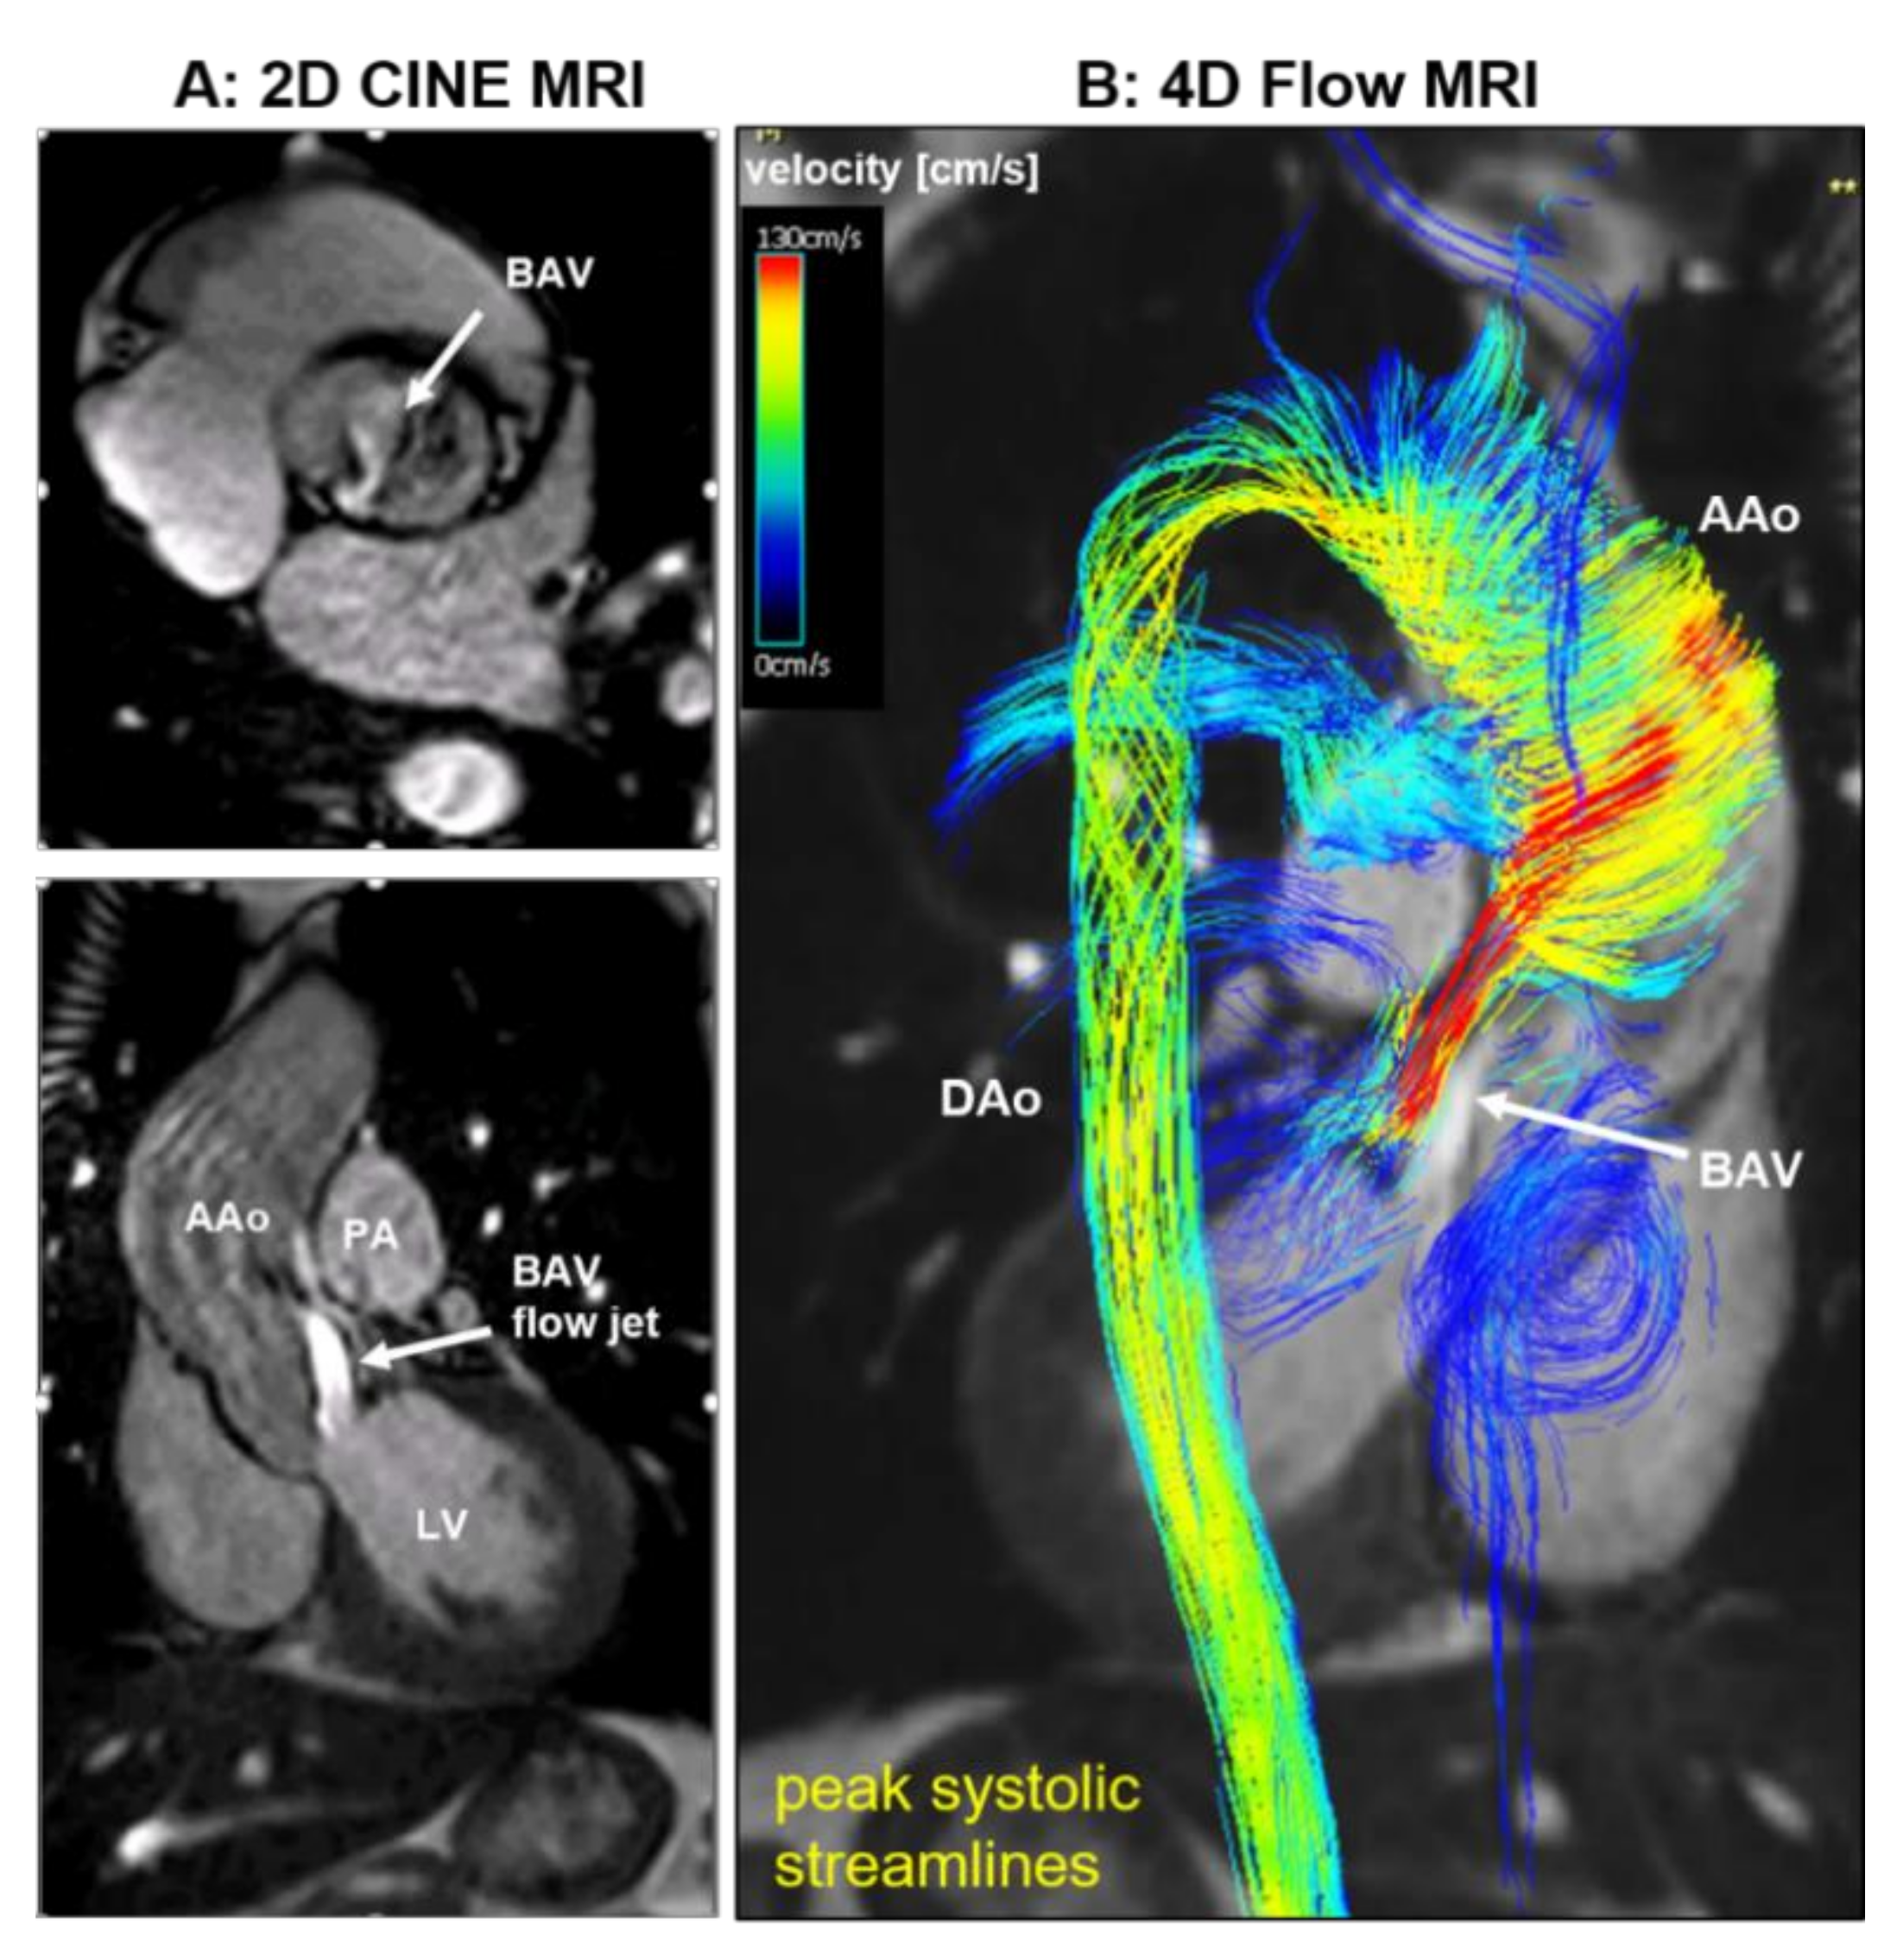

4.3. Imaging of the Aorta